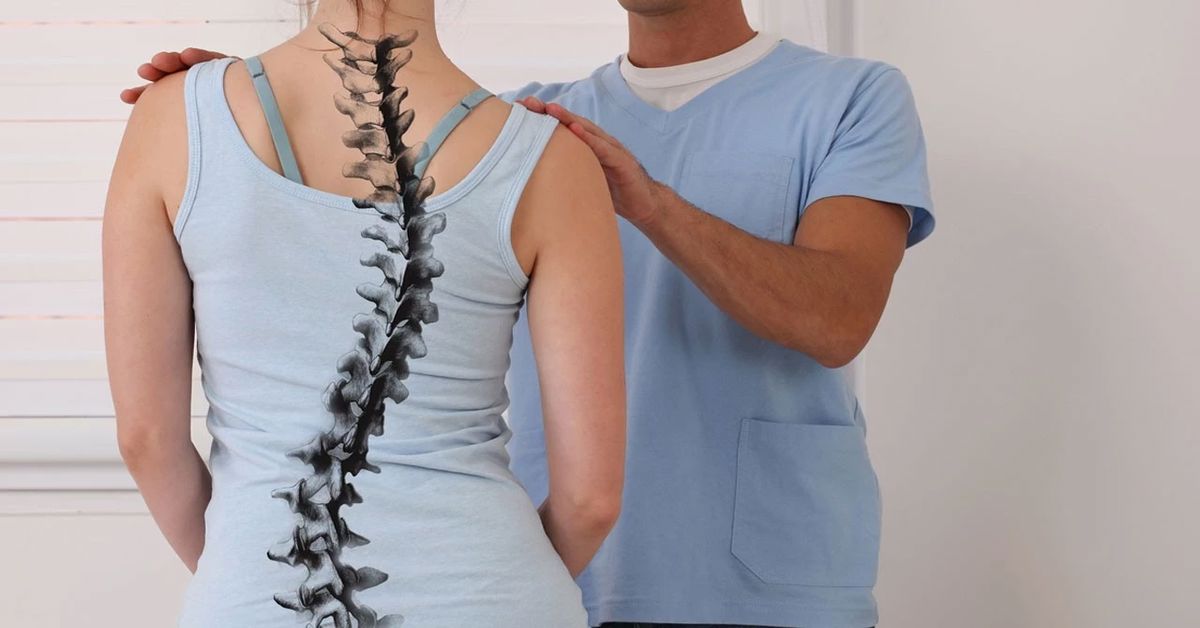

Skolyoz, omurganın yana doğru eğrilmesiyle ortaya çıkan bir omurga rahatsızlığıdır. Normalde omurga önden bakıldığında düz bir hat şeklinde görünür. Ancak skolyoz hastalarında omurga sağa veya sola doğru eğrilir ve bazı durumlarda kendi ekseni etrafında da dönebilir. Bu durum vücut duruşunu ve omuz dengesini etkileyebilir. Bu tablo Skolyoz Hastalığı olarak adlandırılır.

Omurga eğriliği çoğu zaman çocukluk veya ergenlik döneminde fark edilir. İlk belirtiler genellikle duruş bozukluğu şeklinde ortaya çıkar. Omuz seviyelerinde eşitsizlik görülebilir. Bir kürek kemiği diğerine göre daha belirgin durabilir. Bel çukurunda asimetri oluşabilir. Bazı çocuklar sırt ağrısından şikâyet edebilir. Eğrilik ilerledikçe vücut dengesi değişebilir. Bu nedenle erken fark edilmesi büyük önem taşır.

Bazı durumlarda Skolyoz Hastalığı gelişimine farklı nedenler yol açabilir. En sık görülen tipte kesin neden bilinmez. Bu durum idiopatik eğrilik olarak adlandırılır. Ailede benzer sorunların bulunması risk oluşturabilir. Doğuştan omurga gelişim bozuklukları da eğriliğe neden olabilir. Kas ve sinir sistemi hastalıkları omurgayı destekleyen kasların zayıflamasına yol açabilir. Bu durum zamanla eğriliğin ilerlemesine neden olabilir.